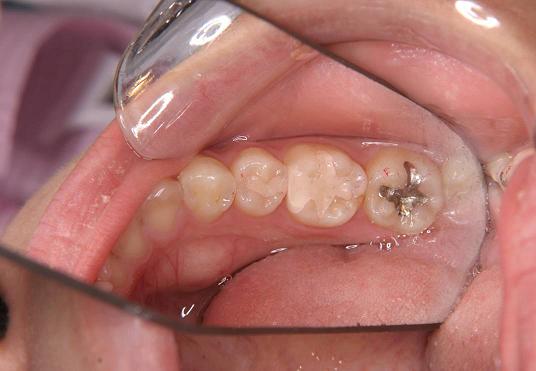

【症例 1】左下5・6番(一部分)2本 (18才,女性)

2.グラディア2本をつけました